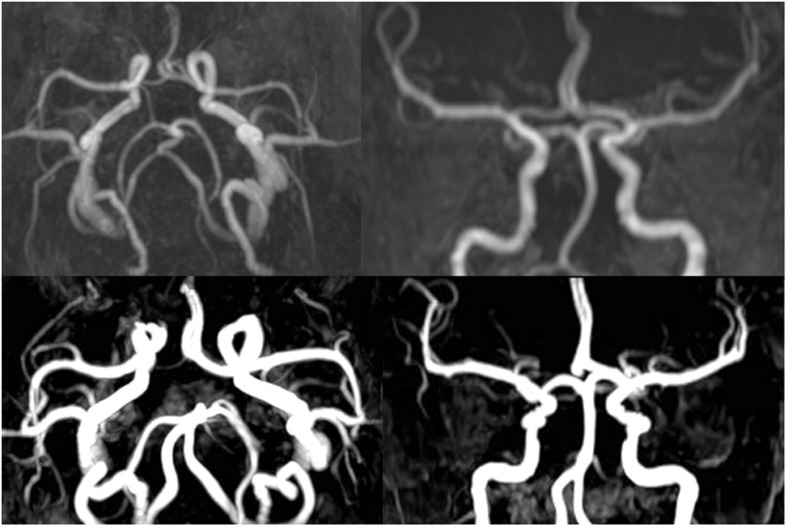

Material and methods: Two healthy volunteers were recruited. Anatomic features and flow directions in the circle of Willis were evaluated with time-of-flight magnetic resonance angiography (MRA) and two-dimensional phase-contrast (2DPC) MRA, respectively. Regional cerebral blood flow was visualized with territorial arterial spin-labeling magnetic resonance imaging (TASL-MRI). TASL-MRI and 2DPC-MRA were performed in three states: at rest, during manual compression of the right carotid artery, and after decompression. In one volunteer, time-space labeling inversion pulse (Time-SLIP) MRA was performed to confirm collateral flow.

Results: During manual carotid compression, in one volunteer, the right thalamus changed to be fed only by the vertebrobasilar system, and the right basal ganglia changed to be fed by the left internal carotid artery. In the other volunteer, the right basal ganglia changed to be fed by the vertebrobasilar system. 2DPC-MRA showed that the flow direction changed in the right A1 segment of the anterior cerebral artery and the right posterior communicating artery. Perfusion patterns and flow directions recovered after decompression. Time-SLIP MRA showed pial vessels and dural collateral circulation when the right carotid artery was manually compressed.

Conclusion: Use of TASL-MRI and 2DPC-MRA was successful for non-invasive visualization of the dynamic changes in regional cerebral blood flow during and after manual carotid compression.